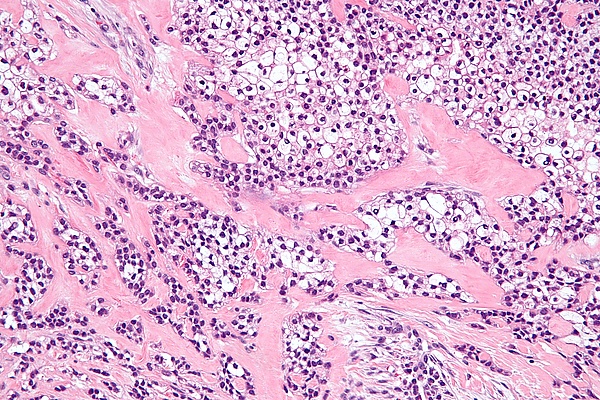

Опухолевые клетки часто располагаются в гнёздах, шнурах (длинных тяжах) и трабекулах (балкообразных структурах), также присутствуют небольшие протоки и кисты. Плоскоклеточные клетки (плоские клетки) и мукоциты (клетки, вырабатывающие слизь) обычно видны как часть структуры опухоли[7].

Одной из уникальных особенностей гиалинизирующей светлоклеточной карциномы является то, что она часто инфильтрирует или распространяется в близлежащие ткани, включая мышцы. В случаях, когда опухоль начинается во рту, она может соединяться с поверхностной выстилкой (эпителием) и распространяться по педжетоидному образцу, то есть опухолевые клетки распространяются по поверхностному слою. Окружающая ткань (называемая стромой) представляет собой смесь плотных, гиалинизированных областей и более рыхлых, фиброзных областей. Такое сочетание типов тканей является характерной чертой этого типа рака[8].